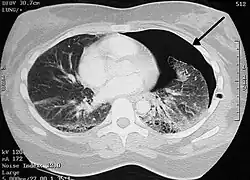

Pneumotórax (do grego, pneumo ar; thorax peitoral) é uma emergência médica causada pela presença de ar entre as membranas que envolvem os pulmões (cavidade pleural) e gera um pulmão colapsado (atelectasia) disfunção nos alvéolos, causada pelo extravasamento de líquido da pleura. Pode afetar um ou ambos pulmões e causar dificuldade para respirar (dispneia).[1]

Um pneumotórax espontâneo primário ocorre sem causa aparente e na ausência de doença pulmonar significativa, enquanto um pneumotórax espontâneo secundário ocorre na presença de doença pulmonar existente, como pode ser o caso da Linfangioleiomiomatose e ou doença pulmonar obstrutiva crônica (DPOC). Um pneumotórax também pode ser causada por trauma físico para o peito (cortante, perfurante ou contusão), ou como uma complicação de uma intervenção médica.

A cavidade pleural é o espaço entre as duas pleuras, que normalmente só deve ser liso e conter líquido pleural. Os pulmões permanecem expandidos na cavidade pleural devido à pressão negativa que varia de -3 a -12 mmHg durante todo o ciclo respiratório. Portanto, a pressão intrapleural negativa contrapõe-se à retração elástica dos pulmões.

A formação do derrame gasoso, após a ruptura pleural, eleva a pressão intrapleural e o pulmão tende ao colapso. Um pneumotórax de grandes proporções ou um pneumotórax aberto tende a aumentar progressivamente a pressão intrapleural ocasionando o colapso do pulmão, desvio do mediastino, compressão das veias, queda do débito cardíaco e hipotensão arterial.